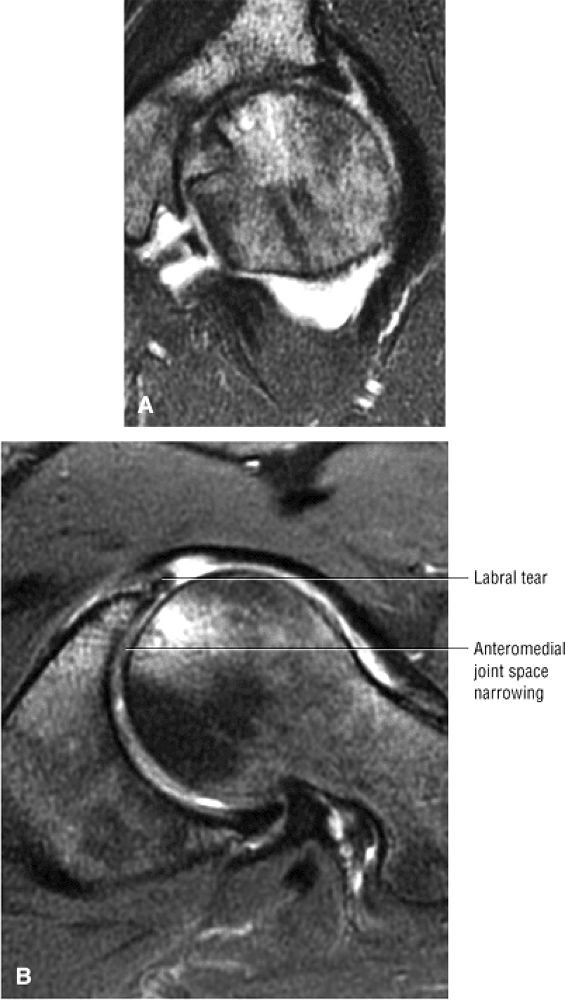

asymmetry in acetabular contour. Acetabular dysplasia is associated with labral tears and early osteoarthritis (OA), a condition known as lateral rim syndrome. Even a mildly abnormal shallow acetabulum predisposes to the development of premature degenerative chondral changes and labral tears. A shallow acetabulum is best visualized on anterior coronal images. Marrow signal throughout the pelvis and femur is often heterogeneous, as the pelvis is a common reservoir for red marrow.

The posterior inferior sublabral sulcus (Fig. 3.60) should not be misinterpreted as a posterior labral tear on axial images.15,16 When depicted, this sublabral groove is seen on one or two axial oblique images superior to the transition between the transverse ligament and the posteroinferior labrum. This sulcus is in fact characterized as a labrocartilaginous cleft and can be shown arthroscopically.

An anterosuperior cleft (Fig. 3.61) may be seen as a normal variant in the presence of a normal lateral acetabular labrum. On anterior coronal or sagittal images, this cleft is seen as a partial undercutting of the labrum on a single image. The extension of fluid into this cleft occurs from the femoral side. It may be more commonly seen in labral hypertrophy associated with mild developmental dysplasia of the hip (DDH).

A transverse ligament-labral junction sulcus is a normal sulcus or recess that may be seen between the transverse ligament and the labrum either anteriorly (Fig. 3.62) or posteriorly (Fig. 3.63). The perilabral sulcus (Fig. 3.64) represents a normal space between the acetabular labrum and capsule visualized on coronal images. The capsule attaches directly to the osseous rim of the acetabulum. A normal sulcus may exist at the junction of the transverse ligament and labrum (see Fig. 3.62) on medial sagittal images. A normal perilabral sulcus is present on coronal images between the capsules and labrum and does not represent a pathologic detachment. This sulcus is a distinct and normal potential separation from the labrum (Fig. 3.65). The

perilabral sulcus is more conspicuous on MR arthrography. In comparison and contrast with the glenohumeral joint of the shoulder, the acetabular labrum of the hip is not critical in providing stability. However, it does maintain a role in creating the vacuum seal of the hip joint. -

An enlarged or hypertrophied labrum may occur in patients with mild DDH.17 We have observed a femoral head chondral crease (Fig. 3.66) in these patients, creating a demarcation trough medial to a femoral head bump immediately proximal to the physeal scar. Patients who demonstrate femoroacetabular impingement (or lateral acetabular rim syndrome in DDH) also have direct impingement between the lateral acetabular labrum and the femoral head.